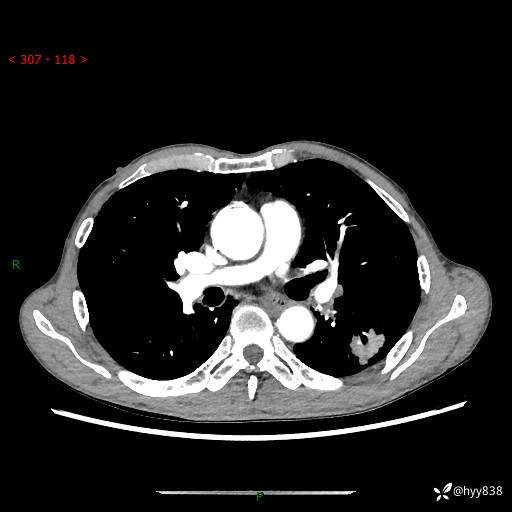

现病史:患者于1月余前无明显诱因出现背部疼痛不适,无明显咳嗽、咳痰、胸闷、咯血、发热等不适,后于2024.5.3至当地市人民医院行胸部CT示:左肺下叶结块,大小约2.2cm*2.6cm,双肺多发小结节,双肺感染性病变,部分纤维增值灶,慢支并双肺局限性肺气肿,肺大泡,纵隔淋巴结增大并部分钙化,冠脉区及大血管壁钙化,双侧胸膜局限性增厚;后口服莫西沙星2周。2024.6.12复查胸部CT示:左肺下叶结块影形态较前饱满,较大截面范围约2.8cm*2.3cm,边缘可见细短毛刺及分叶,性质待查。现患者为求进一步诊治来我院,门诊以“肺占位”收入我科。 起病来,患者精神、食欲、睡眠尚可,大小便正常,体力体重轻微下降。

胸部CT平扫+增强

各期CT值:48hu 100hu 78hu